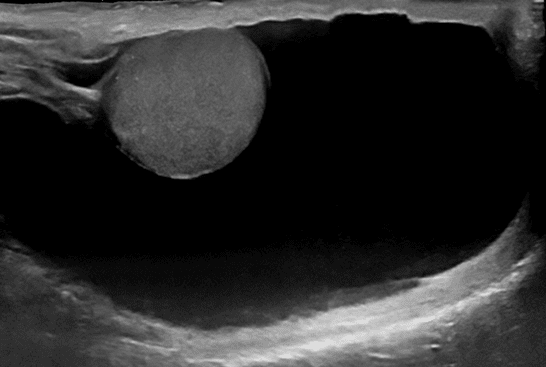

A hydrocele is a collection of fluid in the scrotum that causes swelling, which is soft and often painless. The swelling however may be unsightly and uncomfortable during intercourse or physical activity. A hydrocele is diagnosed by ultrasound, which can be done in the office.

Our specialist performs the aspiration first using ultrasound-guidance. The ultrasound shows precisely the location of the needle so that the testicle or adjacent structures do not get punctured, essentially eliminating any risk thereof. Make sure that your specialist performing this procedure is trained in ultrasound-guided procedures.

Most urologist will not offer aspiration and sclerotherapy. For urologists that do, they do not perform the procedure with the same technique as our specialist. There are several reasons why sclerotherapy by your urologist failed. The main reason is the lack of ultrasound guidance. Ultrasound confirms that all of the hydrocele fluid has been removed before injecting the medication. Any fluid left behind will dilute the medication rendering it inactive. Urologist perform this procedure blindly with a needle. There is no way to know if there is any fluid left in this manner. Needle aspiration is also not as effective in removing all of the fluid.

Our specialist performs the aspiration first using ultrasound-guidance. Ultrasound is used throughout the procedure to make sure the procedure is performed adequately and safely. The ultrasound shows precisely the location of the tube so that the testicle and adjacent structures do not get punctured, essentially eliminating any risks. Make sure that your specialist performing this procedure is trained in ultrasound-guided procedures. Our specialist performs more sclerotherapy treatments than any other specialist.